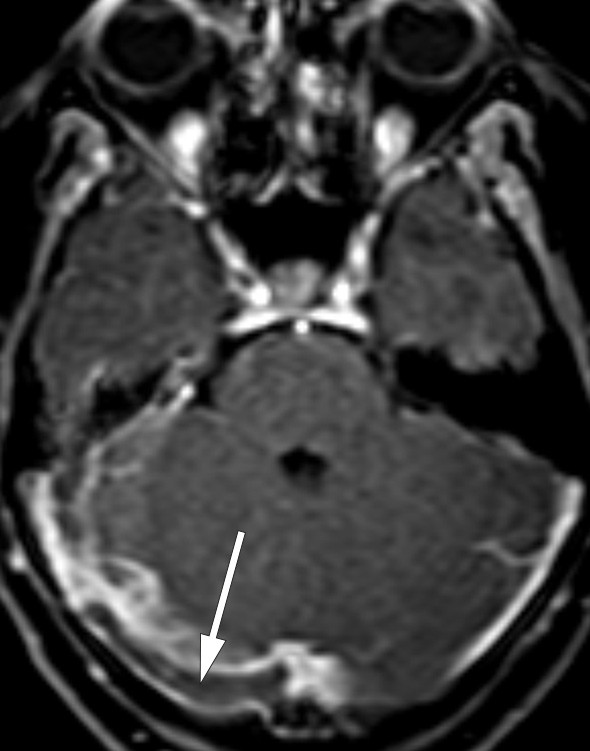

A small number of cases that have been examined anatomically and with CT or MRI scans indicate that prosopagnosia is usually associated with bilateral medial occipitotemporal lesions. There are also rare cases caused by unilateral injury, almost always on the right side (14). Our patient’s thrombus was in fact in the right transverse sinus (Fig. 1). Venous drainage from the temporal lobe into the transverse sinus occurs via the vein of Labbé (inferior anastomotic vein), and venous stasis here can cause circulatory disturbances in associated brain tissue. MRI revealed no diffusion abnormalities or other parenchymal changes. However, no signal was detected in the vein of Labbé on the side in question, whereas a good signal was obtained in the contralateral vein (Fig. 3). On balance, we consider it likely that the MRI findings are related to the patient’s cognitive symptoms.

Figure 3  Venous MR angiogram (TOF sequence) shows good filling of the contralateral vein of Labbé (arrow), but no signal in…

Figure 3 Venous MR angiogram (TOF sequence) shows good filling of the contralateral vein of Labbé (arrow), but no signal in the ipsilateral vein